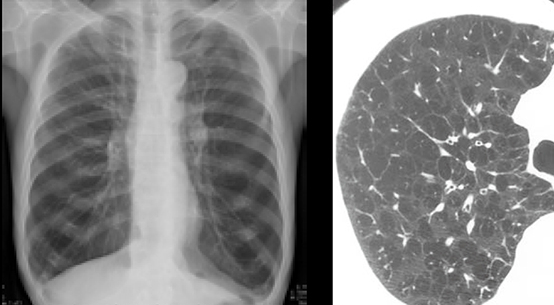

(9) 폐섬유증

폐섬유증은 폐조직에 섬유화가 발생하여 폐의 기능을 저하시키는 질병으로, 호흡 곤란, 기침 가래 등의 증상이 나타납니다. 이 질환은 환경적, 유전적, 방사선 노출 등 다양한 원인이 있습니다.